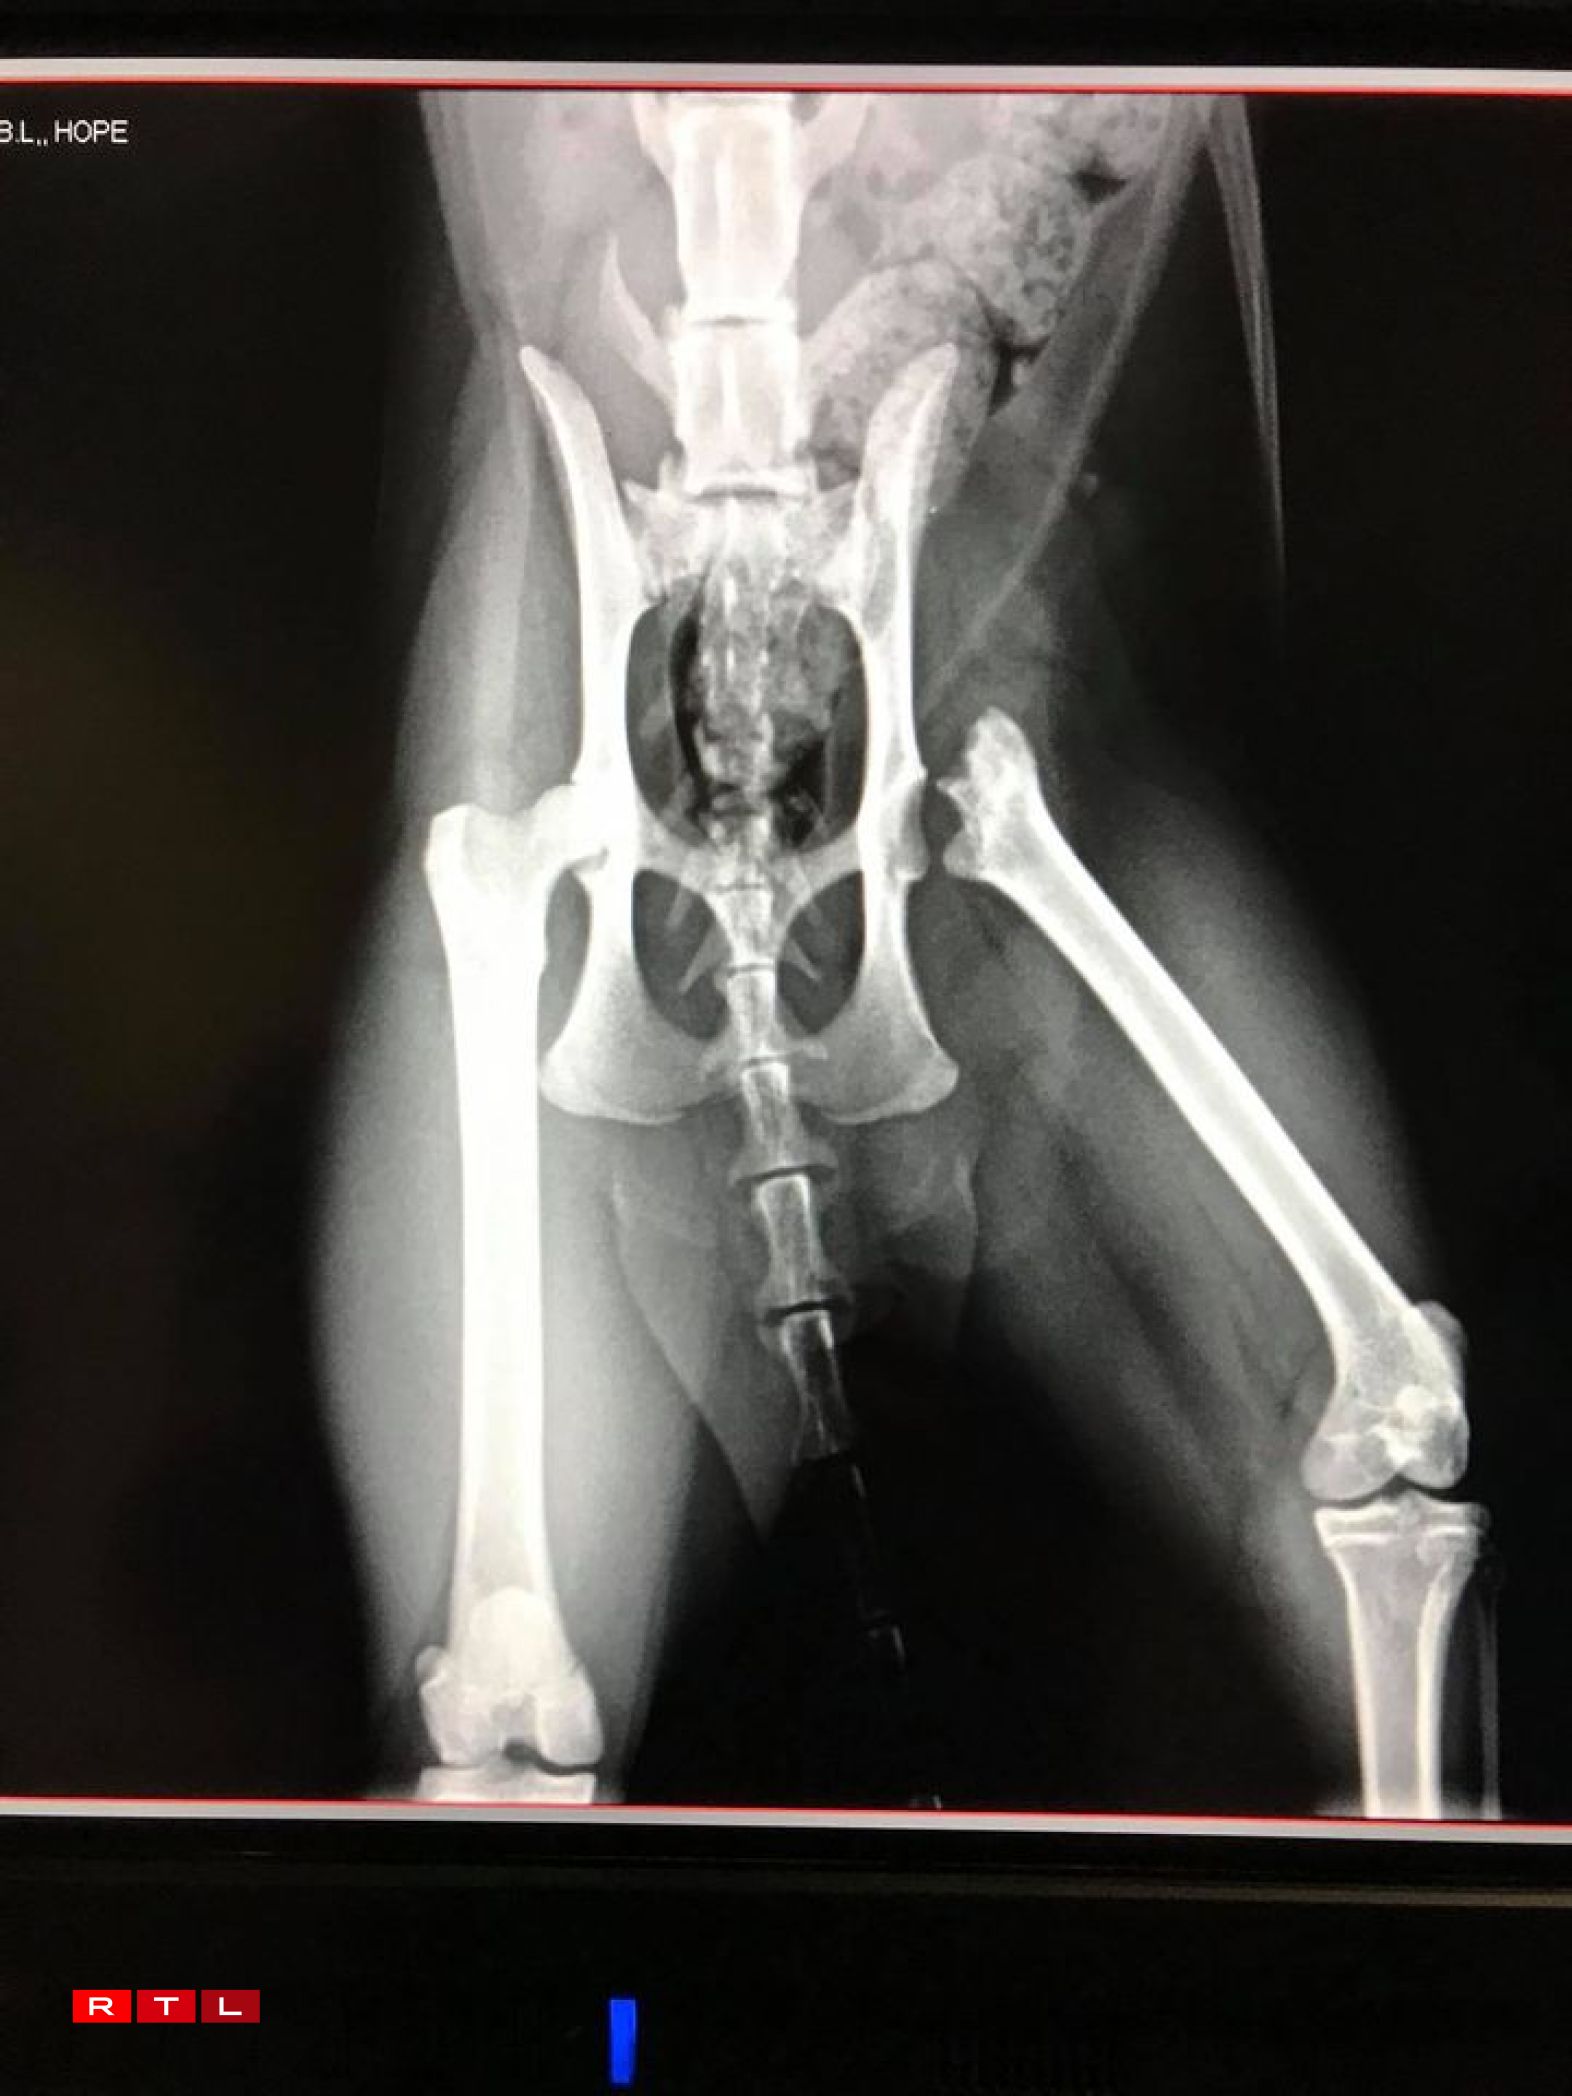

Dann hëlt d’ASBL och krank an accidentéiert Kaze bei sech op, fir se ze fleegen, wéi d’Baghira, dat de 6. Abrëll 2018 zu Buerschent beim Schlass fonnt ginn ass oder d’Hope de 27. Oktober 2020 zu Esch. Fir déi, déi kee Besëtzer hunn, gëtt dann duerno en neit Doheem gesicht, wa se dann och kastréiert a gechipt sinn. Am Allgemengen huelen d’Membere vum Comité just Kazen an d’Fleeg. Si haten awer och scho Villercher oder Hënn. Vill Kaze kënne si net zu gläicher Zäit ophuelen. Dat läit dorunner, datt dës Associatioun nach kleng ass a well si net déi néideg finanziell Moyenen hunn. Deemno wéi schlëmm d’Blessure vun de Kaze sinn, bleiwe si fir ëmmer an dëse Fleegefamillen.

Vill Leit ginn dovunner aus, datt d’ASBL Vermëssten Déiere just eng Säit op Facebook ass. Doduerch kréie si dann och net esou vill Donen, op déi si awer ugewise sinn. Kazen, déi vun engem Auto ugestouss gi sinn, mussen dacks operéiert ginn. An dat gëtt deier. D’Adoptiounsfraisen, déi si froen, decken dës Käschten net.